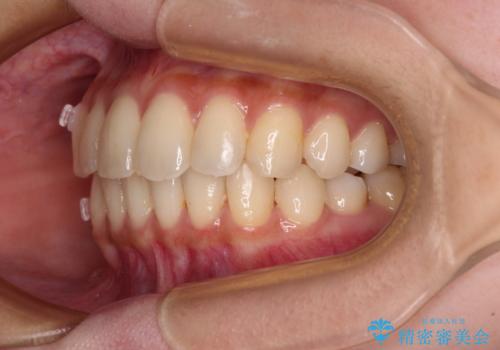

- 前歯のデコボコと強い咬みしめを気にして来院された患者様です。

インビザラインを用いて、前歯の叢生を解消するとともに、ディープバイトを改善していくこととしました。

海外へ転居する予定があったため、1日22時間以上の装着時間をしっかりと守っていただき、予定期間よりも早く、思っていた以上にきれいに仕上げることができました。